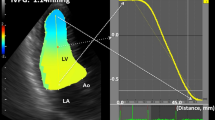

Pattern A

The intraventricular flow is entirely or predominantly directed toward the apex throughout the IVR period, and red-encoded flow is widely distributed in all parts of the LV cavity. In the streamline map of VFM, IRF is organized along parallel streamlines heading towards the apex (Fig. 1, top row). In the vortex map, no vortex can be found during the whole IVR period (Fig. 1, bottom row), or very few small transient vortices can be found in one or more but not all image frames during the IVR period, which may occur in any part of the LV cavity.

The frame-by-frame analysis of IRF corresponding to pattern A in a 71-year-old male normal subject from apical long-axis view. The parallel streamlines in the LV chamber indicate that IRF is directed toward the apex (top row), and no vortex can be found throughout the IVR period (bottom row). AO: aorta, LA: left atrium, LV: left ventricle.

All normal subjects and patients with normal mitral inflow pattern demonstrated an IRF corresponding to pattern A. Also, most of patients with impaired LV relaxation showed pattern A. The inhomogenous LV activation-inactivation may give rise to intraventricular pressure gradient from the LV base toward the apex during IVR4. Normally, the pressure gradient generates suction and contributes to the occurrence of apically directed IRF1,2,3,4. Although the rate of relaxation is reduced in patients with impaired LV relaxation, the ability to decrease LV pressure should be preserved to some extent and intraventricular pressure gradient would be generated during the IVR period. Accordingly, in these subjects, IRF was the non-vortical laminar flow directed from base to apex (Fig. 1). One or more small transient vortices that might randomly occur anywhere in the LV cavity could be found during the IVR period. The area of the vortex was very small and the duration was very short. The physiological or slight pathological nonuniformity of electrical and mechanical events in space and in time might be responsible for the occurrence of the small transient vortex.